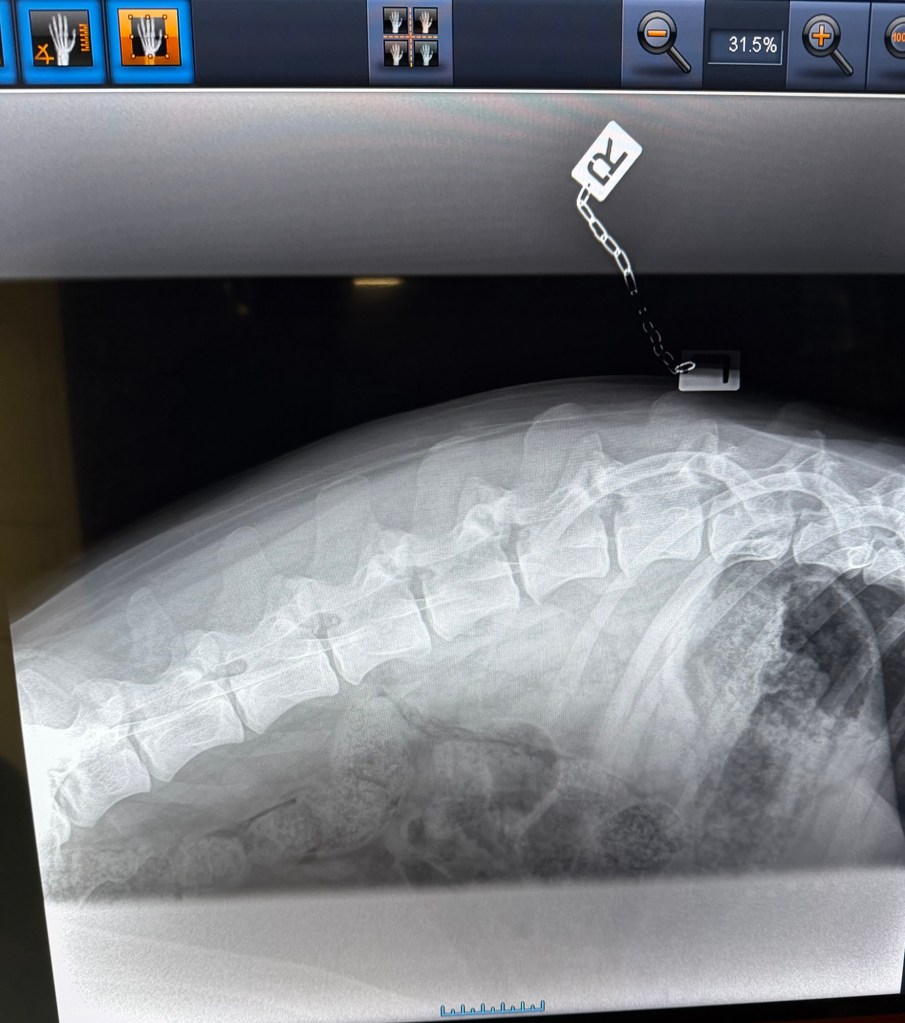

Geri var på ny røntgen nå i november 2025, i en alder av 3år og 8måneder. Dette for å være ansvarlig og forsikre meg om at det ikke blir avl på foreldredyr som har feil utvikling og avdekke svakheter hvis de eksisterer.

Det viste seg å være meget positive resultater (legger ved noen av bildene). Ingen forkalkninger og fremdeles fine albuer, ingen forandring fra 18 måneder HD/AD røntgen til nesten 4års alder. Hun har også en meget fin rygg, og spesielt god og robust lenderygg (bak) som er et fokus område for schæferhunden.